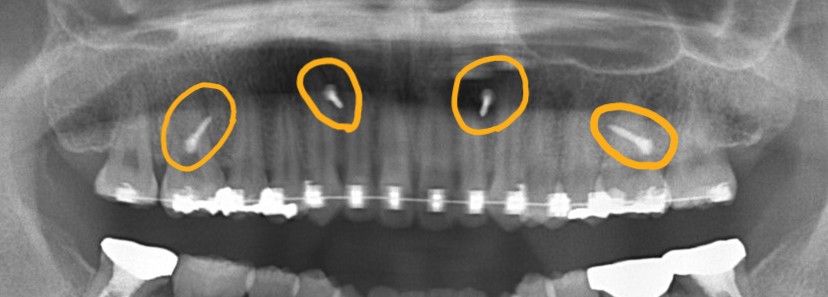

レントゲン写真で確認すると、

一応、Eラインが引ける状態です。

この患者さんの場合、

【診断】

#1.上下顎前突

#2.open bite (開口)傾向

#3.ガミースマイル

と診断しました。